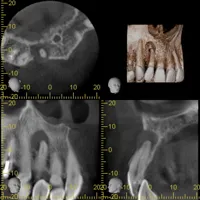

根管治療を成功させるためには、歯の根の構造を正確に把握し清掃することが求められます。 なぜなら、歯の根は人によって異なるためです。根がまっすぐ伸びているものばかりではなく、枝分かれしていたり、意外な角度で曲がっていたり、細すぎたりなど、歯によって個性があります。

上記のように、人によって異なる根の構造を把握するために、多くの歯科医院がレントゲン撮影を試みるのですが、レントゲンでは平面としてしか捉えることができないため、正確な根の構造を知ることは極めて困難だと言えます。 当院が導入している歯科用CTでは、歯の内部を立体的に撮影可能であり、根の構造を正確 に把握することができるため、根管治療の成功に大きく貢献しています。 根の構造を的確に把握することが成功の鍵を握る根管治療では、歯科用CTは必要不可欠だと言っても過言ではありません。

レントゲンで撮影した場合

歯科用CTで撮影した場合